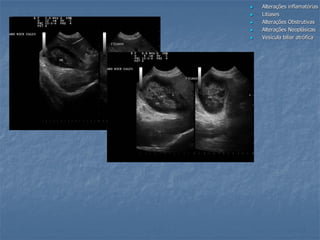

Obstrução Biliar Extra-Hepática (cães)

 Sinais de obstrução

Pesquisa da etiologia da obstrução/ compressão:

- Inflamatória (fígado, pâncreas e TGI)

- Cálculos

- Tumores (fígado, pâncreas, linfonodos, duodeno)

cálculos abscesso

DBC

gordura

pancreatite

colelitíase

colangiocarcinoma

colangite e pancreatiteInflamação pielogranulomatosa com fibrose